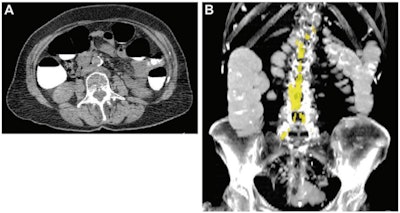

Abdominal aortic calcium in a 74-year-old woman who underwent CT colonography for colon cancer screening in 2008 and suffered a subsequent acute myocardial infarction one year later. (A) Axial noncontrast CT image at the L3 level. (B) Coronal maximum intensity projection CT image shows quantification of aortic calcium (yellow). The patient's aortic calcium Agatston score was 4137, while the 90% specificity threshold aortic calcium Agatston score was 735. Images and caption courtesy of the RSNA.Lee's group conducted a study that included 9,223 asymptomatic adults who underwent abdominal CT colonography as part of routine colon cancer screening between 2004 and 2016. The researchers used an automated deep learning and image processing algorithm that was developed, trained, and tested with muscle, abdominal fat, and atherosclerosis body composition data at the U.S. National Institutes of Health Clinical Center using information from another group of individuals, not Lee's study cohort.